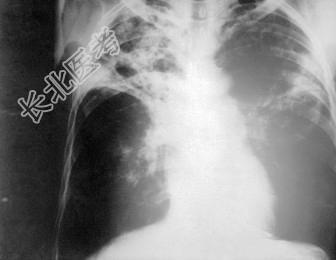

- 单项选择题患者,男性, 21岁,咳嗽伴午后低热1周入院, X线胸片如图所示,最可能的诊断是 ( )

D、肺结核